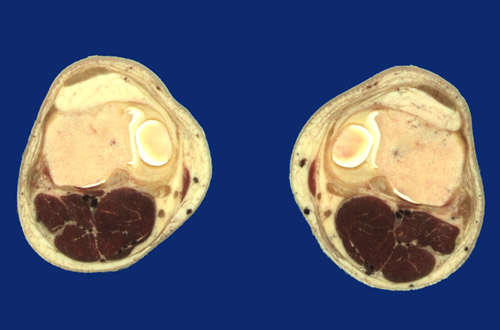

Identify the following regions in the image above: Patellar ligament - Infrapatellar fat pad - Articular cartilage - Popliteal vessels - Small saphenous vein - Great saphenous vein - Medial meniscus - Medial femoral condyle - Tibial plateau - Sartorius - Semitendinosus tendon - Gastrocnemius, medial head - Gastrocnemius, lateral head - Plantaris - Popliteus - Iliotibial tract